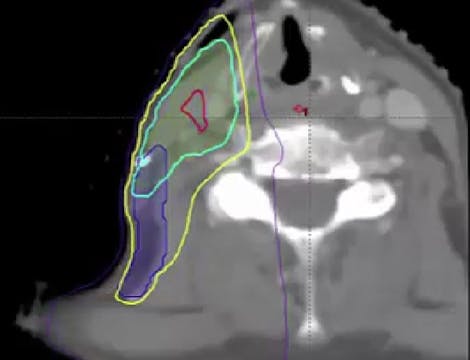

06/30/2025 - Dr. David Sher - Radiation Oncology - Head & Neck

Chartrounds US - Head and Neck Cancer